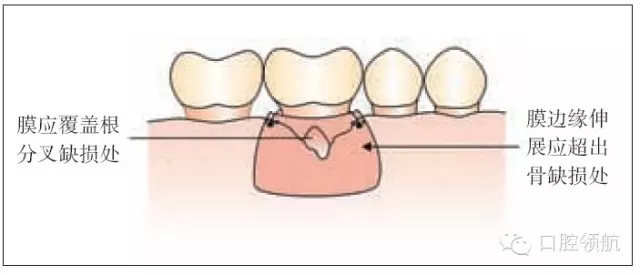

圖26.3 引導組織再生術:膜的放置

引導組織再生術(GTR)將細胞的移行重新排序,使來源于牙周韌帶的細胞能夠增殖并且移行到愈合位點,形成新的而非修復好的牙周膜(圖26.1)。

這項技術包括膜的放置,它隔開移行的上皮和結(jié)締組織,在清潔的牙根表面創(chuàng)造一個空間。它使細胞重新附著然后成熟形成新的牙周韌帶纖維,插入到骨組織。

·修剪膜使它大小既能覆蓋缺損同時輕輕延伸超過它的邊緣(圖26.3)。